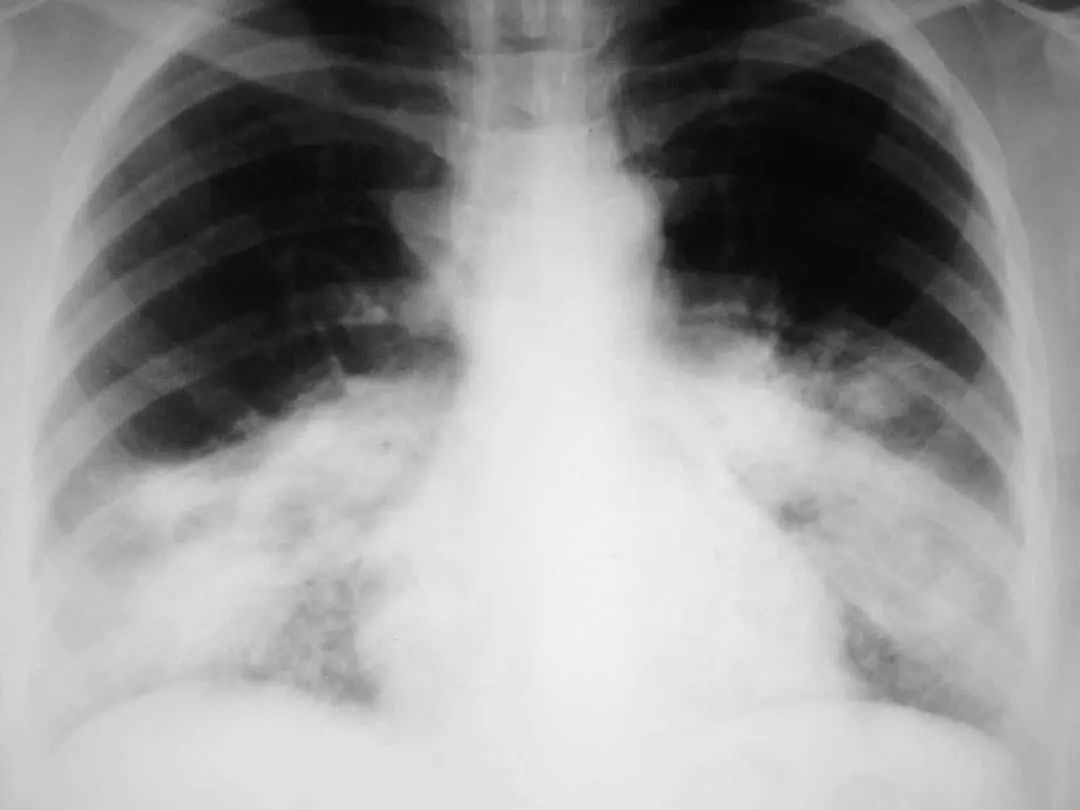

图1.5 40岁肺炎衣原体患者。胸片显示右上、中、下叶多灶性斑片状实变。

图1.6 38岁的支原体肺炎患者。胸部X线片显示左下叶模糊不透明影。